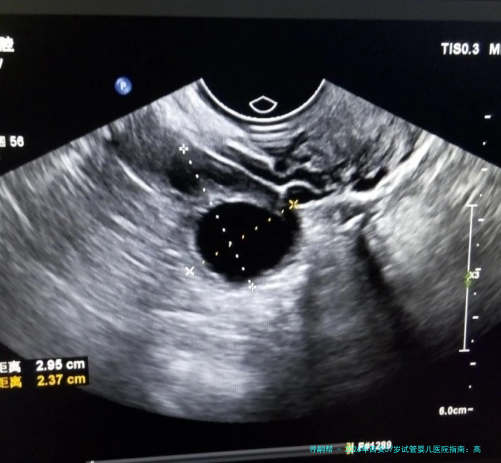

| 阴道B超监测排卵 | 150 | 80 | 100 | 90-120 |